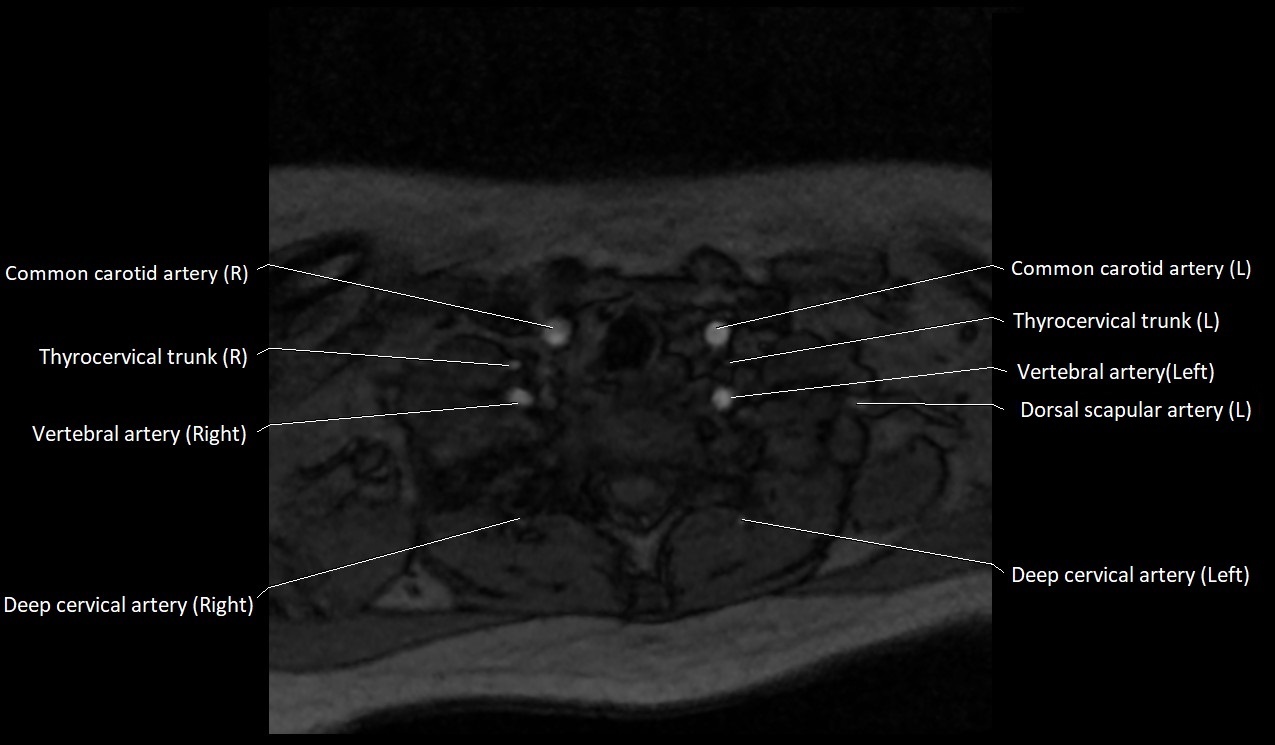

CT image

image